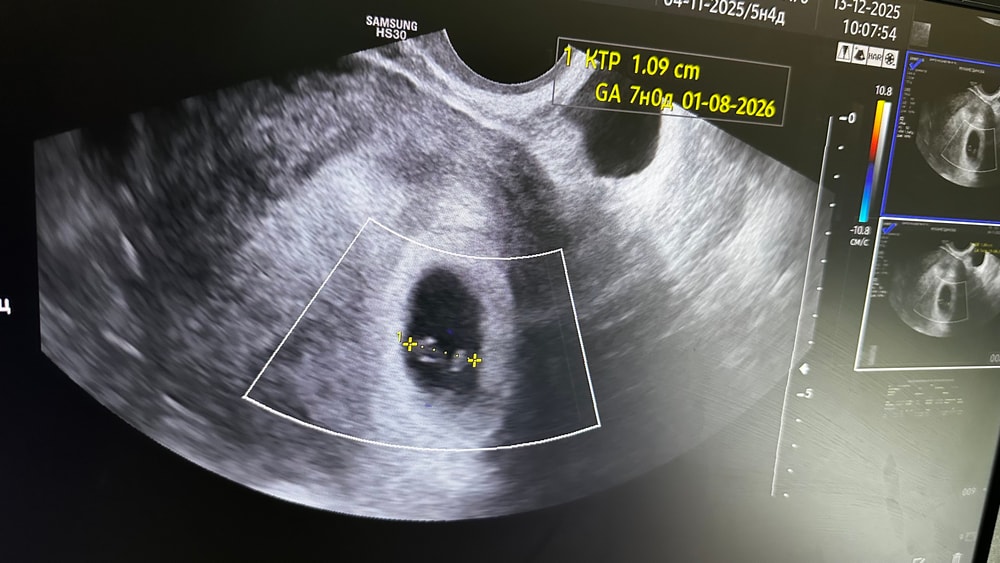

Была госпитализирована вечером в пятницу в гинекологическое отделение после УЗИ (неразвивающаяся беременность, 8-9 недель) и получения результатов анализов.